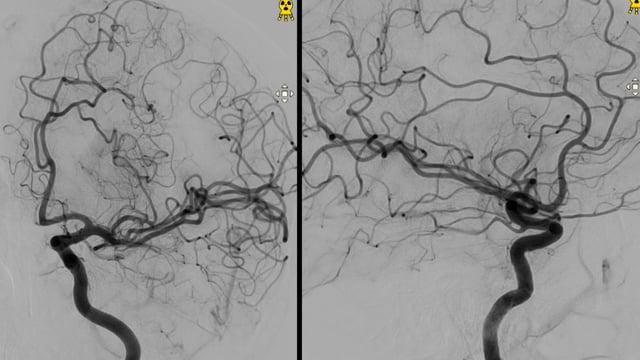

Small A1 aneurysm

ICA-M1 intracranial dissection EVT